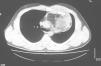

Radiología Casos en imagen 2

Casos en imagen 2

Case 2

J. Cubero Carraleroa, JM. Abadal Villayandrea, V. Guadaño Salvadoresa

a Servicio de Radiodiagnóstico. Hospital Severo Ochoa. Madrid. España.